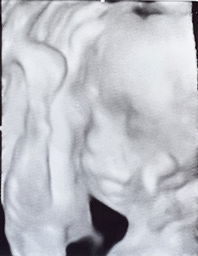

7months napo ang tyan ko at pinapatest po ako ng Ob ko ng OGTT ayos lang ba nadikona ito gawin?